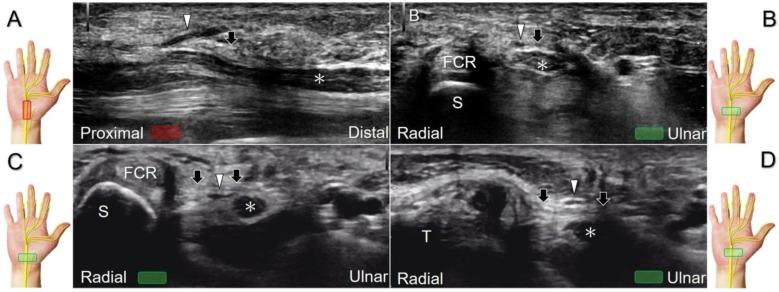

手腕/手部远端周围神经病变的超声成像与引导

超声已成为一种极具价值的工具,用于腕部区域周围神经病变的成像,特别是对于诸如腕管综合征和尺神经管综合征等常见病症。大量研究表明,神经在卡压部位近端肿胀、边界不清和平扁是神经卡压的特征。然而,关于腕部和手部的小神经或终末神经的信息却很匮乏。本文旨在通过全面概述这些神经卡压的扫描技术、病理学和引导注射方法来填补这一知识空白。本综述详细阐述了正中神经(主干、掌皮支和返支)、尺神经(主干、浅支、深支、掌尺皮支和背尺皮支)、桡浅神经、骨间后神经、掌总/指固有神经和背总/指固有神经。一系列超声图像用于详细说明这些技术。最后,超声检查结果补充了电诊断研究,有助于更好地理解整个临床情况,而超声引导下的干预措施对于治疗相关神经病变是安全有效的。